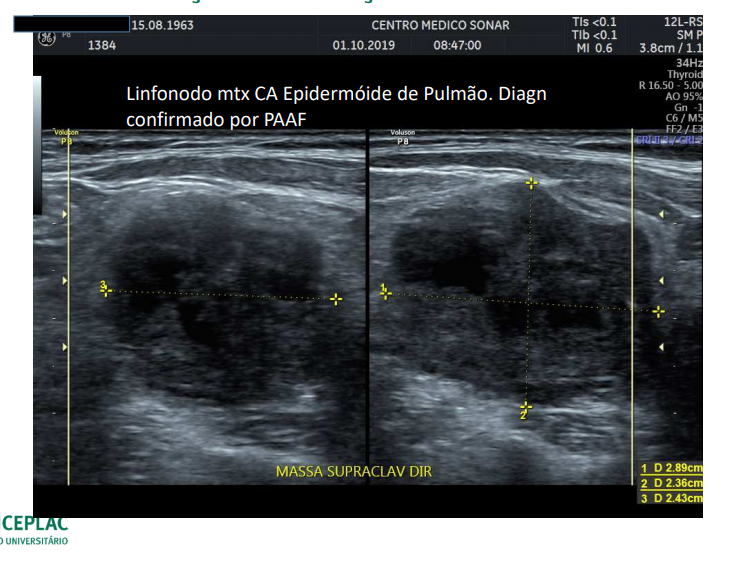

Podemos verificar linfadenomegalia no USG? É um diganóstico diferencial para massa cervical?

Sim!

Quando devemos suspeitar de malignidade em linfonodomegalia?

Quando o diametro perpendicular a pele for mais que o paralelo.

Quando a vertical for maior que a horizontal.